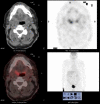

Extramedullary plasmacytoma of the tongue base